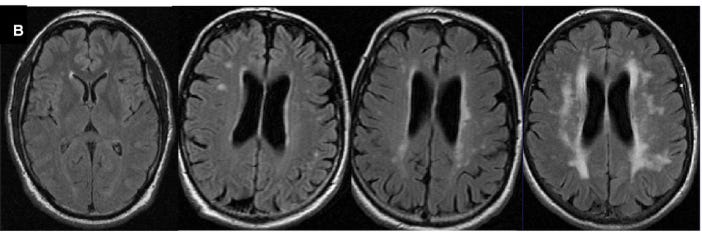

White matter hyperintensities are so named because they appear as bright areas in the brain’s white matter on water-sensitive MRI sequences (such as T2-weighted and FLAIR images, in the image below), reflecting increased tissue water from chronic small-vessel injury.